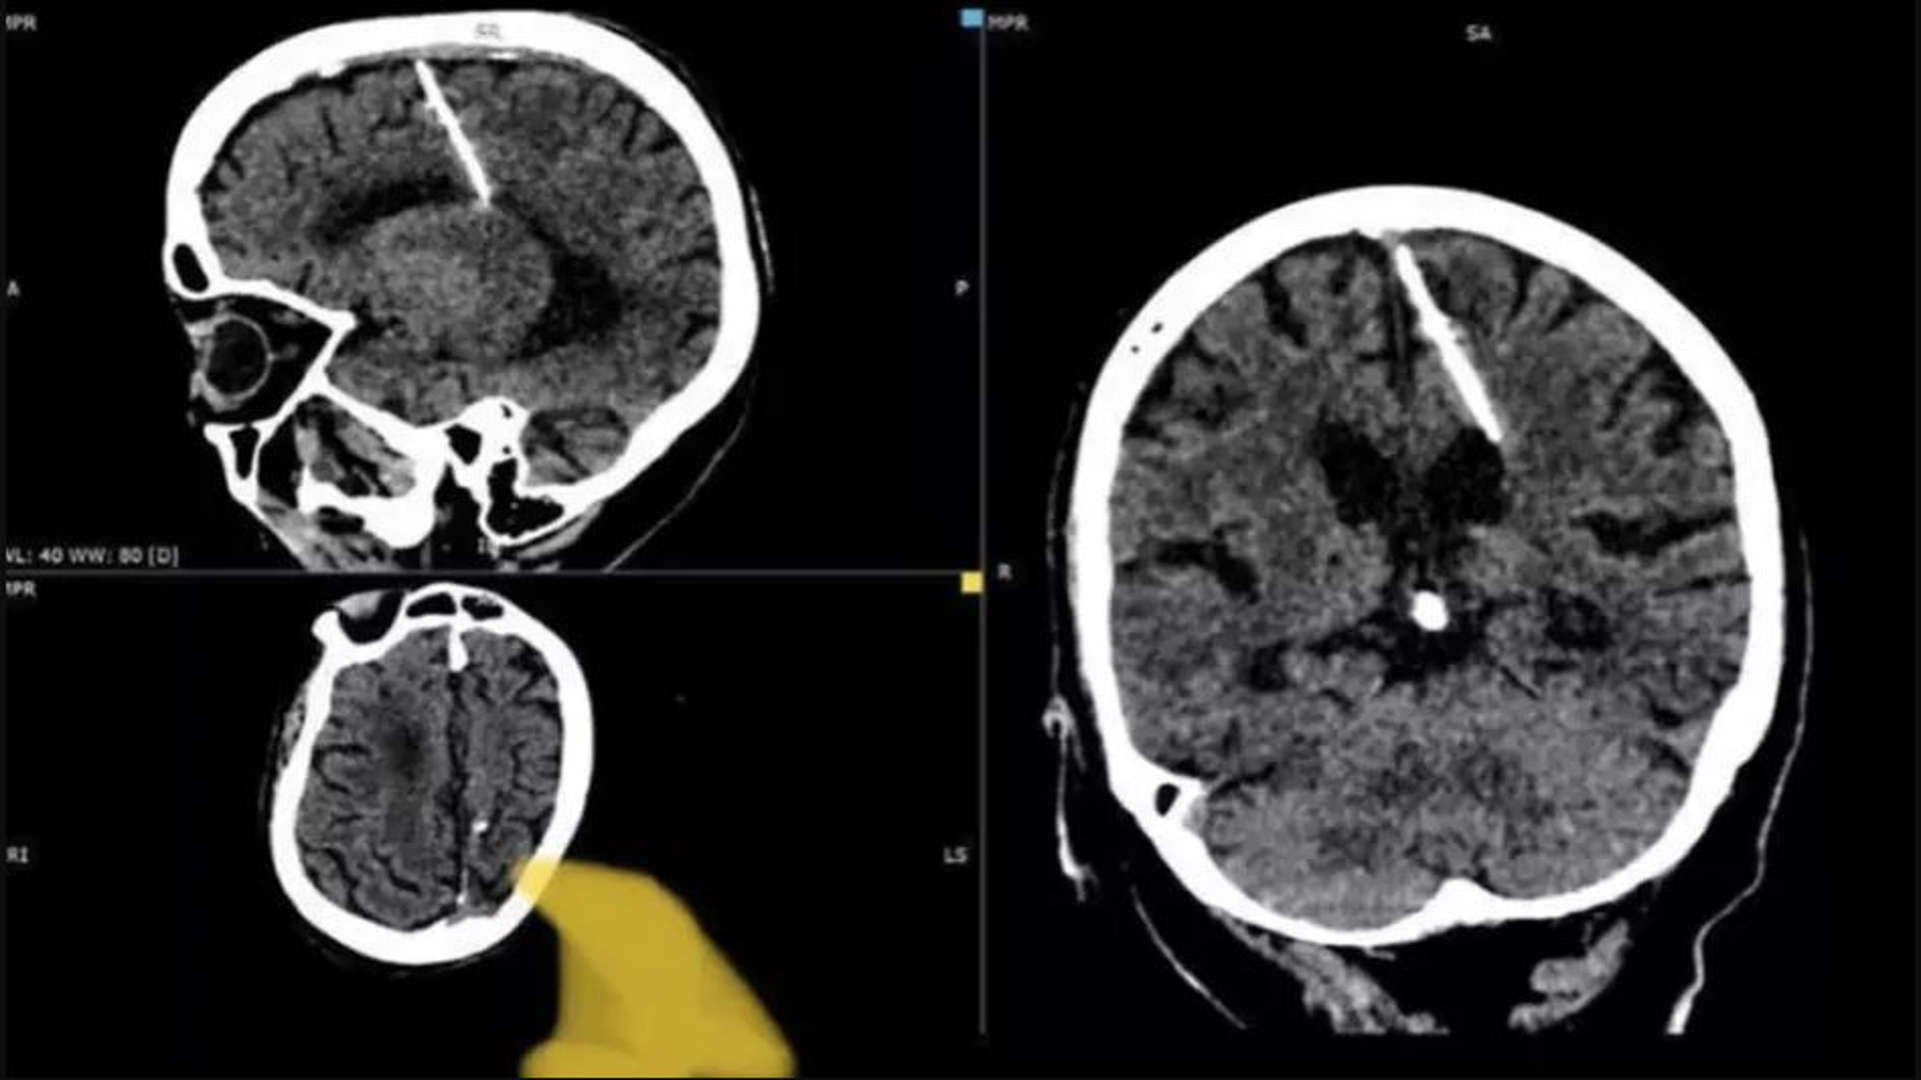

Rusia – Un escalofriante caso ha sorprendido a los médicos rusos, luego de encontrar una aguja en el cerebro de una mujer que la ha tenido por 80 años; sospechan que sus padres intentaron matarla de bebé con ella. Los hechos ocurrieron en el Lejano Oriente de Rusia, donde una mujer adulta mayor se sometió a una tomografía computarizada.

Al revisar sus estudios, los médicos descubrieron que tenía una aguja en el cerebro y que la había tenido por 80 años. De acuerdo con Russia Today, la mujer podría haber sido víctima de un intento de infanticidio que no tuvo resultados, por parte de sus propios padres.

Durante la Segunda Guerra Mundial, época en que la mujer era una bebé, Rusia atravesaba una fuerte hambruna. En esta época, era común el asesinato de bebés a manos de sus propios padres por la difícil situación del país. Es por ello que autoridades sospechan que la mujer podría haber sido una potencial víctima, pero sobrevivió al intento de sus padres de acabar con su vida cuando era bebé. De acuerdo con medios locales, la mujer goza de buena salud y nunca ha sufrido ni siquiera dolores de cabeza o migrañas, por lo que se ha tomado la decisión de no retirar la aguja en el cerebro que le fue encontrada. *MM